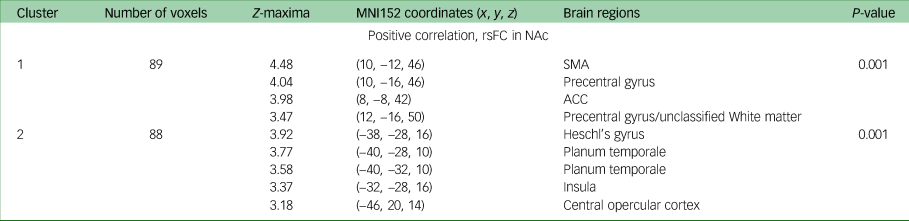

Seed-based correlation analysis: rsFC association with anhedonia change (week 0 to week 16)

Change in DARS score from baseline to week 16 was positively correlated with baseline rsFC between the NAc and the supplementary motor area (P = 0.001), precentral gyrus (P = 0.001), and anterior and posterior cingulate cortices (P = 0.001) when controlling for both age and gender; and age, gender and MADRS score. Additionally, when controlling for age, gender and MADRS score (but neither age nor gender alone), change in DARS score was positively associated with baseline rsFC between the NAc and Heschl's gyrus (P = 0.001), planum temporale (P = 0.001), insula (P = 0.001) and central opercular cortex. All results are presented in Table 3, and presented visually in Fig. 1.

Table 3 MNI152 coordinates of Z-maxima for association between DARS score change and rsFC, baseline to week 16a

MNI, Montreal Neurological Institute; DARS, Dimensional Anhedonia Rating Scale; rsFC, resting-state functional connectivity; NAc, nucleus accumbens; SMA, supplementary motor area; ACC, anterior cingulate cortex.

a. Controlled for Montgomery–Åsberg Depression Rating Scale, gender and age.